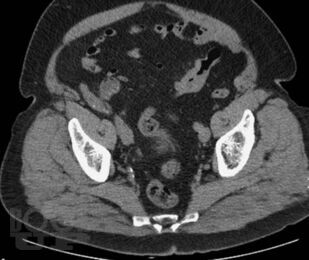

В книге приведены типичные клинико-рентгенологические ситуации, взятые авторами из повседневной практической работы в отделе лучевых методов диагностики и лечения Института хирургии им. А.В. Вишневского. Проанализированный материал охватывает хирургические заболевания органов брюшной полости и забрюшинного пространства вне острых или неотложных состояний. В первой части книги читателю предоставлена максимальная возможность сделать самостоятельное заключение о заболевании после анализа жалоб пациентов, анамнеза заболевания и приведенных изображений рентгеновских и КТ-исследований. Во второй части книги читатель может проверить правильность хода своих рассуждений и собственного заключения. Решение подобных ситуационных задач, несомненно, послужит большим подспорьем как начинающим, так и опытным врачам лучевой диагностики в их практической работе.